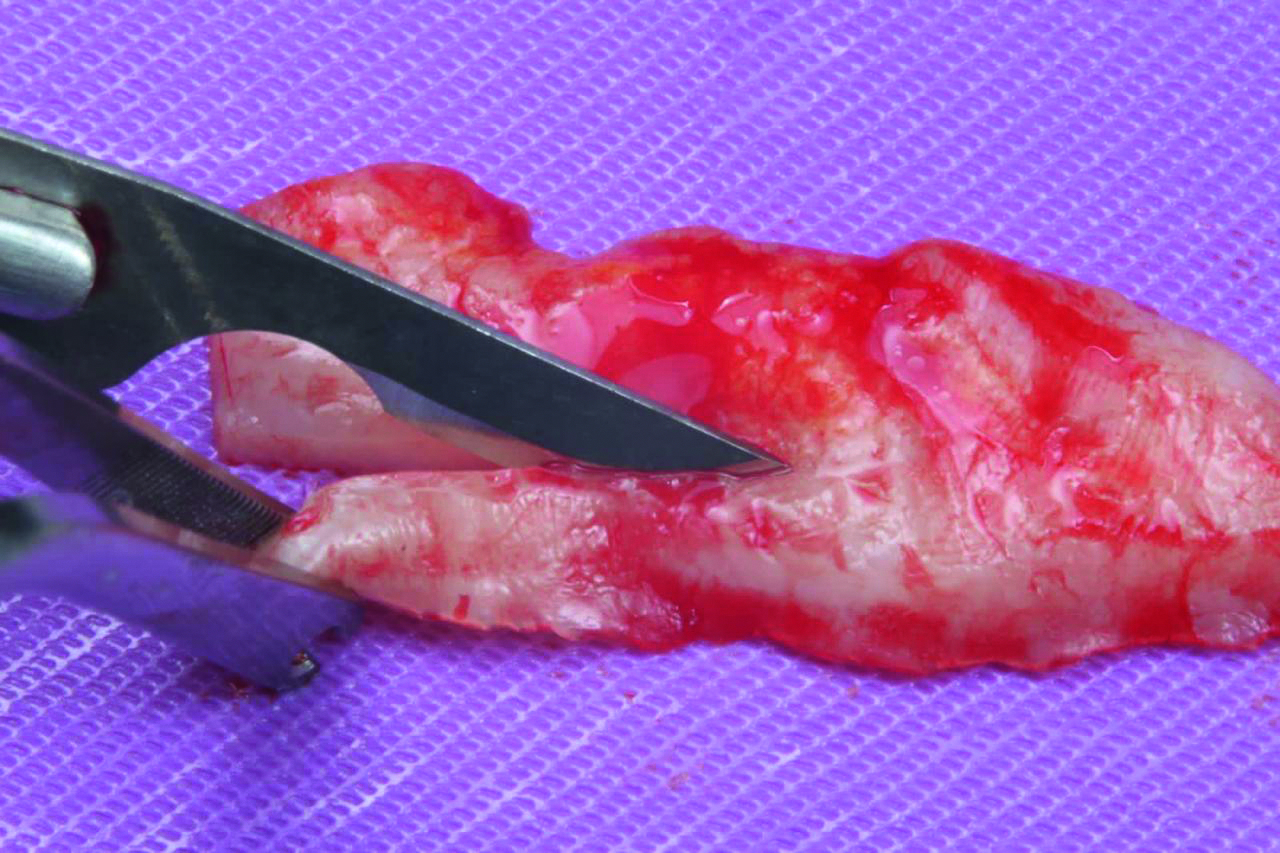

• Соединительнотканный трансплантат (СТТ)

• Получение СТТ

• Твердое небо и бугор верхней челюсти

• Защита донорской области

• Заменители СТТ